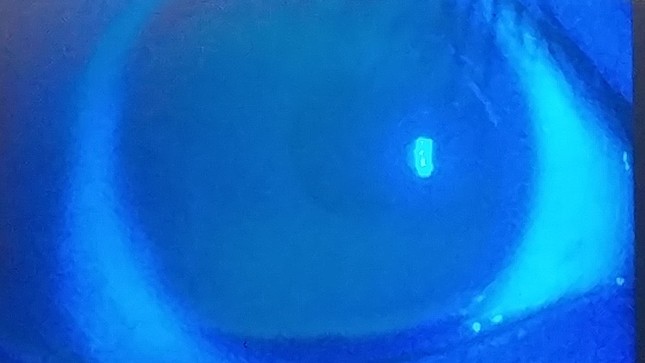

• 医師からのチェックを受けた記者の角膜。傷はなく「異常なし」の診断結果だった

医師からのチェックを受けた記者の角膜。傷はなく「異常なし」の診断結果だった

検査は専用の染色液を目につけて、角膜やまぶたの裏にある「結膜」についた傷をチェックする。日頃からデスクワークが多いJ-CASTトレンド記者も不安な心境で検査を受けてみたが、診断結果は「異常なし」。撮影された目の画像には傷のない綺麗な角膜が写されていて、ホッと胸をなでおろした。